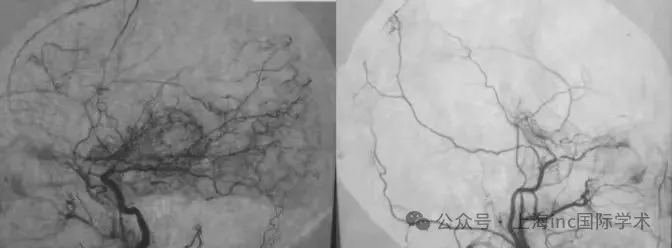

A:春奈术前右颈血管造影显示,在颈内动脉末端顶部,血管烟雾弥漫性发育,大脑中动脉扩张;B&C:浩一术前影像

如下图所示中细密、不规则的网状血管,日本医生最早发现了这种情况,觉得像喷出的烟雾(日语:moyamoya),因此给它取名"烟雾病"。

烟雾病血管造影影像